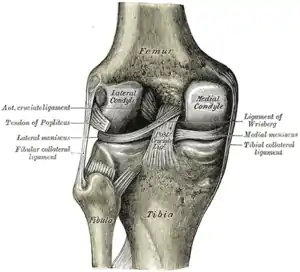

The lateral meniscus is grooved laterally for the tendon of the popliteus, which separates it from the fibular collateral ligament.

Its anterior end is attached in front of the intercondyloid eminence of the tibia, lateral to, and behind, the anterior cruciate ligament, with which it blends; the posterior end is attached behind the intercondyloid eminence of the tibia and in front of the posterior end of the medial meniscus.

Close to its posterior attachment it sends off a strong fasciculus, the ligament of Wrisberg, which passes upward and medialward, to be inserted into the medial condyle of the femur, immediately behind the attachment of the posterior cruciate ligament.

Left knee joint from behind, showing interior ligaments.

Left knee joint from behind, showing interior ligaments. Right knee-joint, from the front, showing interior ligaments.